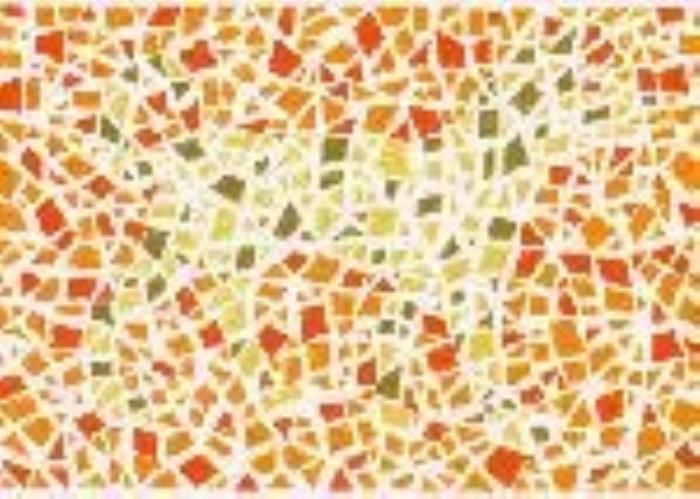

·形状图1

结果:正常看到的是正方形、三角形

·形状图2

结果:正常看到的是一大一小,两个圆形